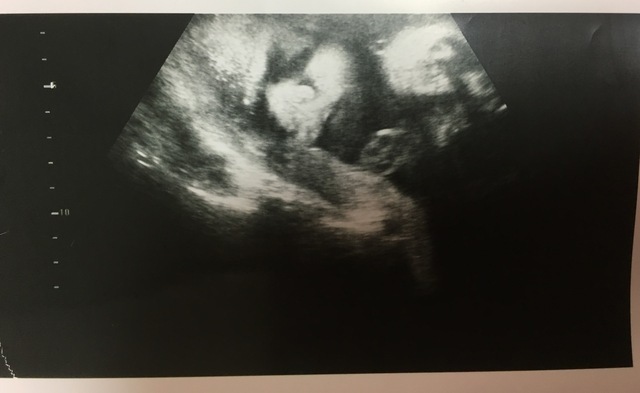

31週2日(31w2d・男の子)|花織 さん(23歳)

エコー写真撮影時のエピソード:

出産自体初めてのことで、 20代で子どもを産むことに色々不安を抱いていました。ですが、このエコーを見たとき、 初めて手がハッキリと見えて、小さいのにすごくしっかりしてることがわかりました。

母親としての実感が芽生えてはいましたが、改めて子どもを育てて行くという実感を感じることが出来ました。

このエコーのお陰ですごく元気づけられ、 産休に入るまでの間も仕事を続けることができ、 出産の一週間前まで働きました。 無理することはしないでできることをしながら 生まれてくる子どもの為に働けました。この時、 見えた手はすごく私に勇気をくれました。